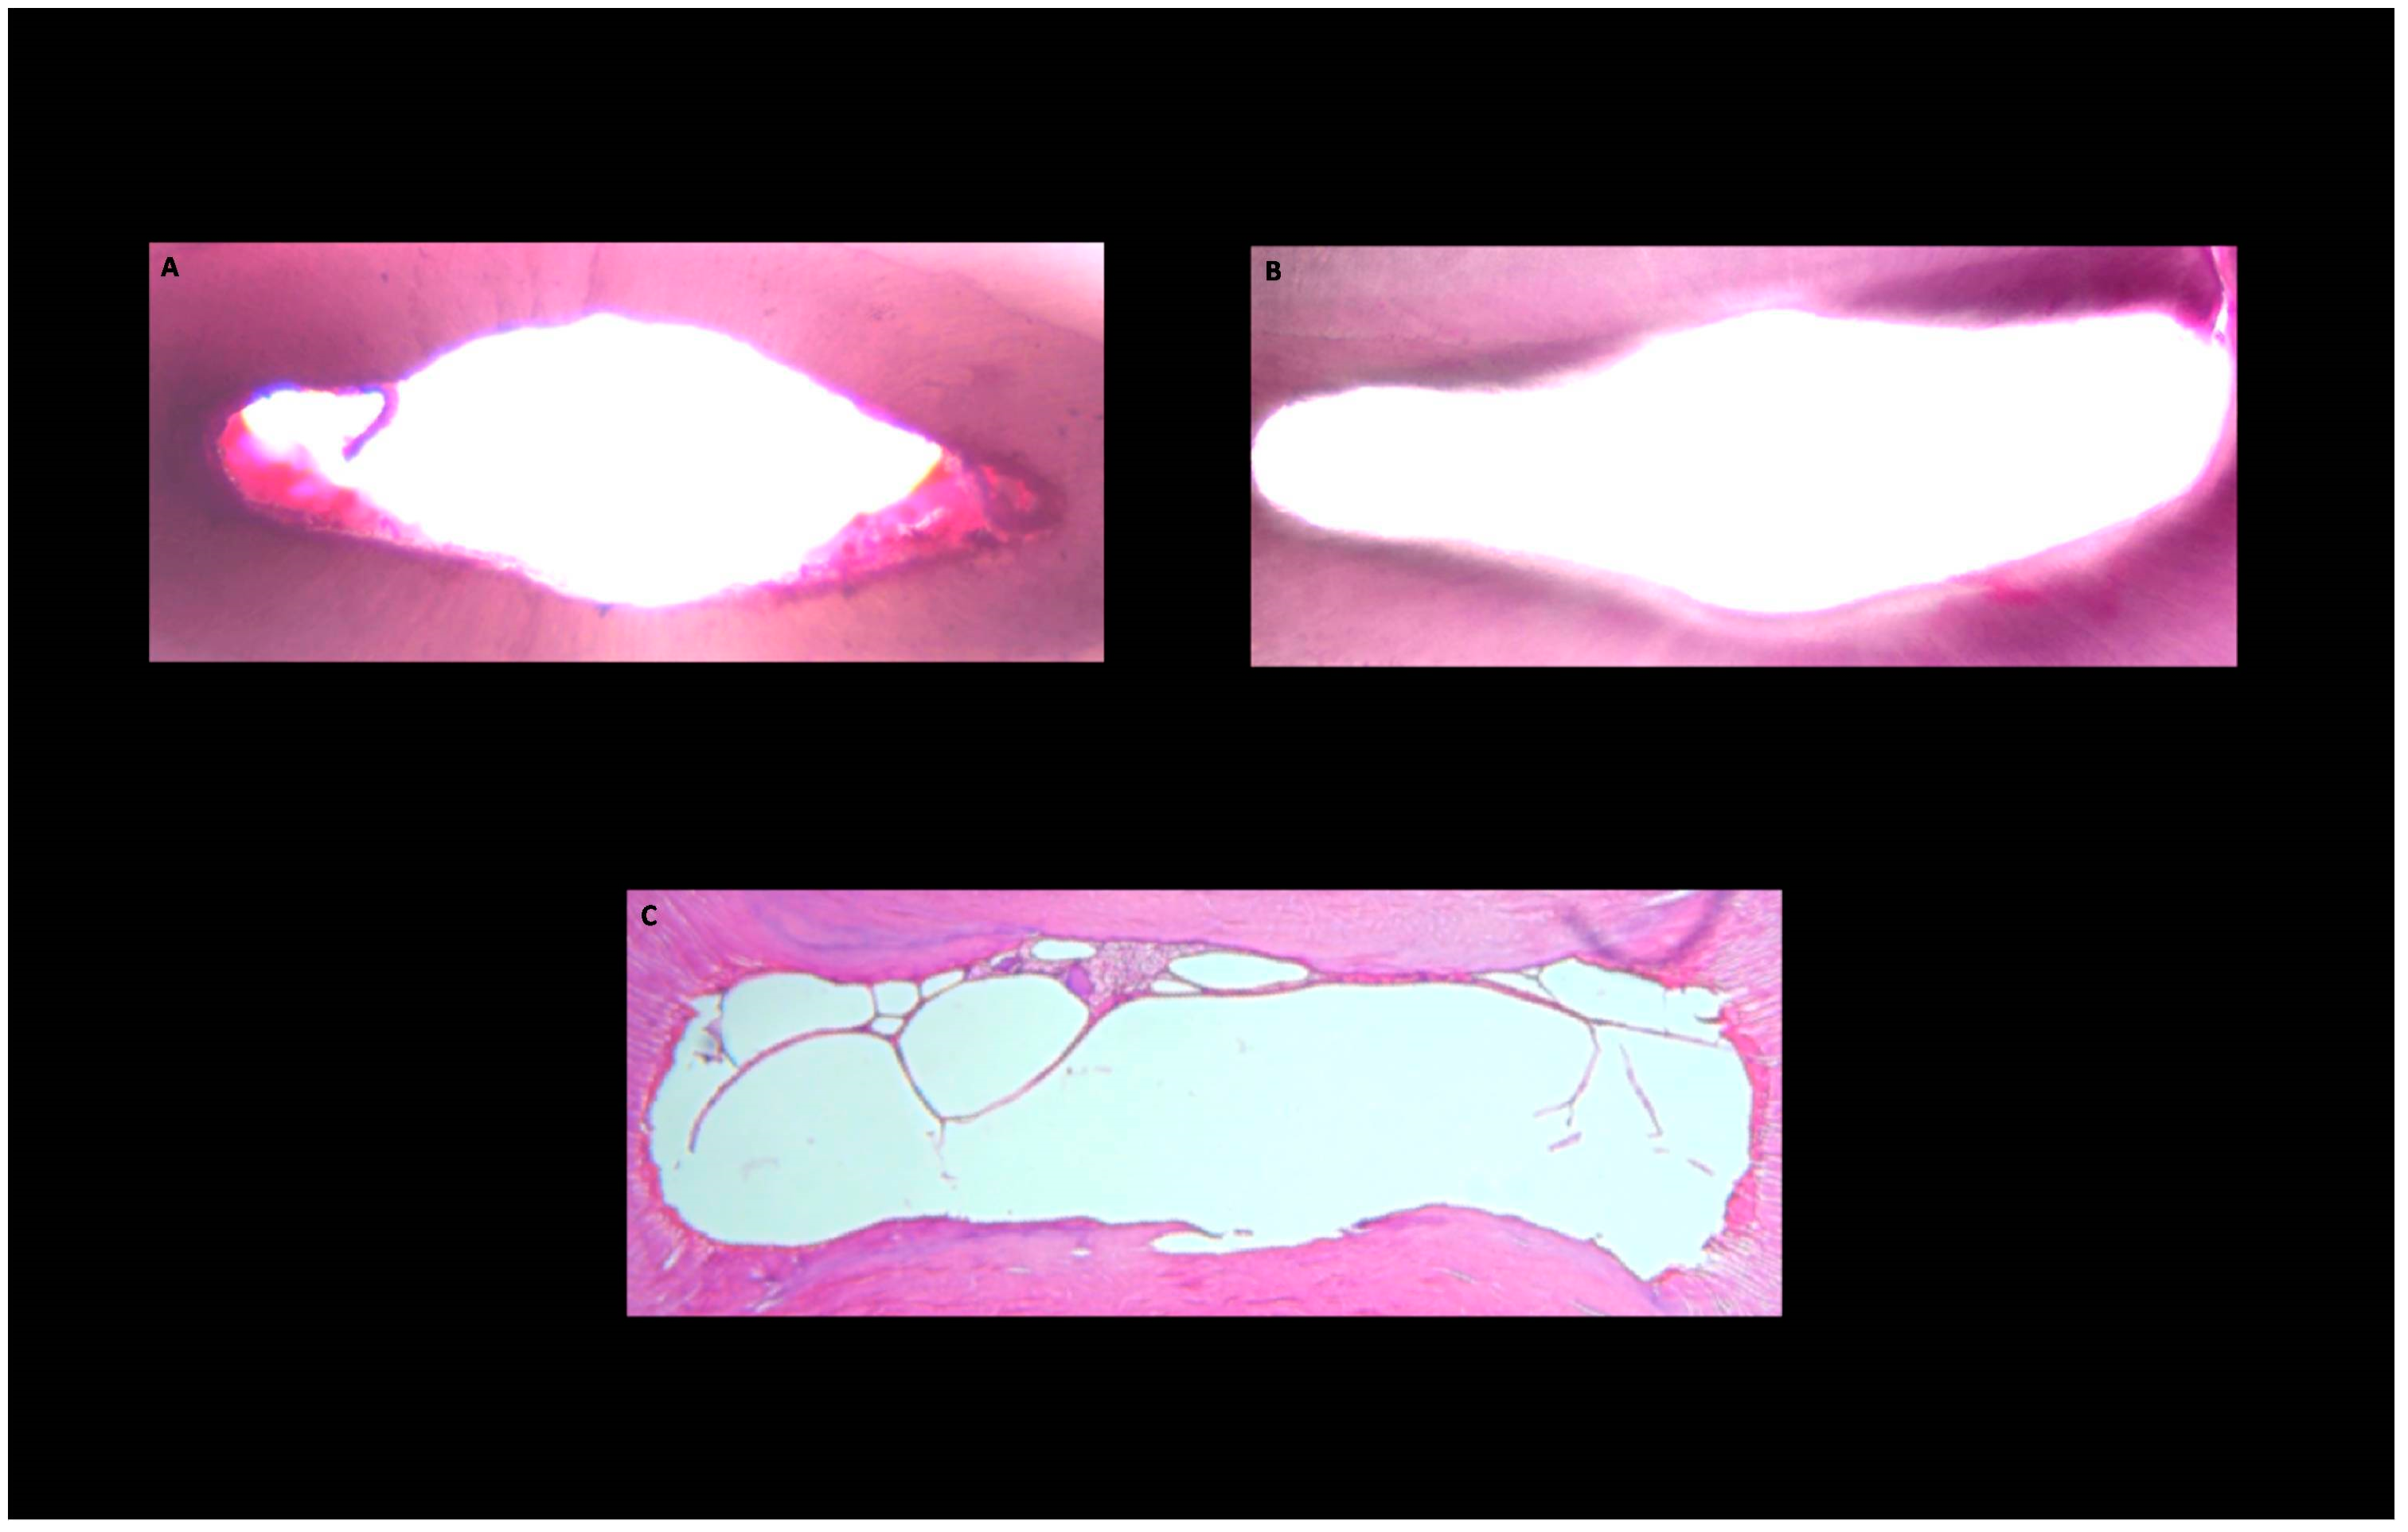

2.3. Evaluation of Root Canal Walls Cleanliness